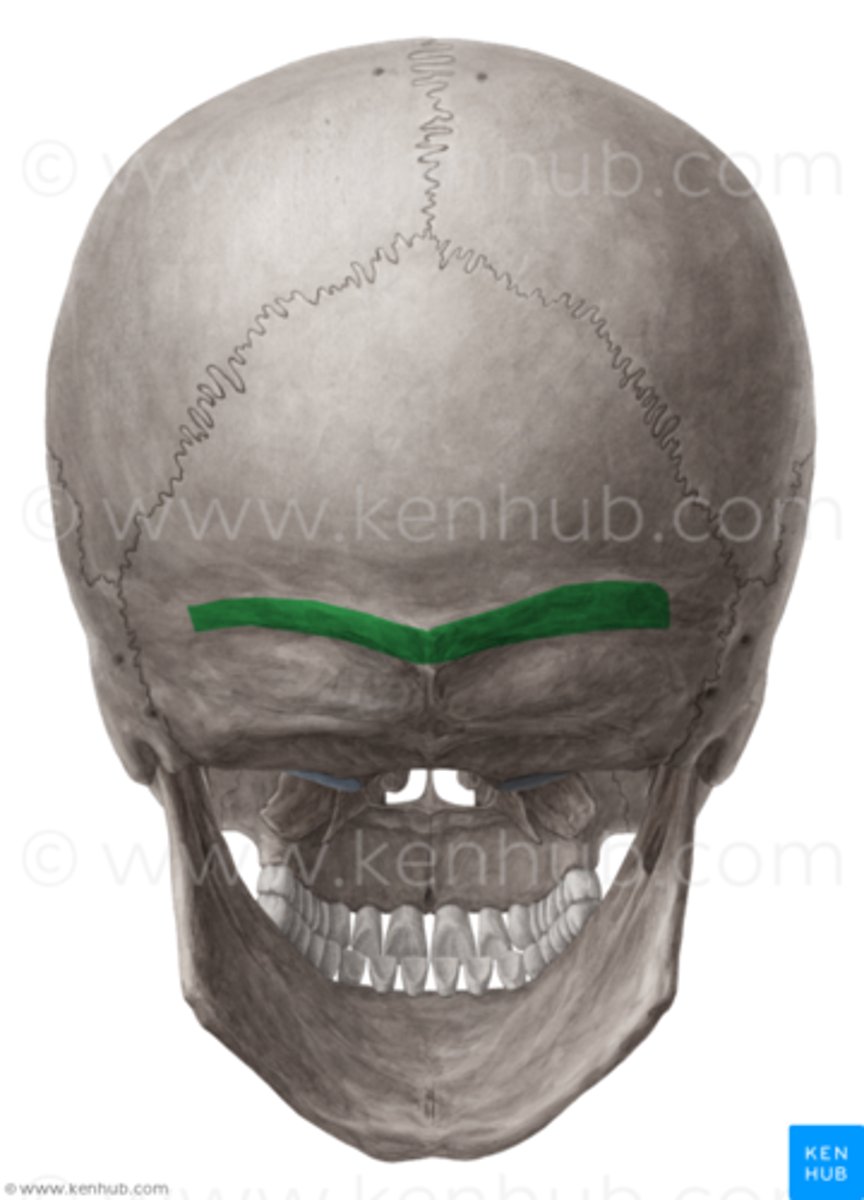

Supraorbital margin of frontal bone

the sharp ridge that forms the border between the forehead and inside of the orbit